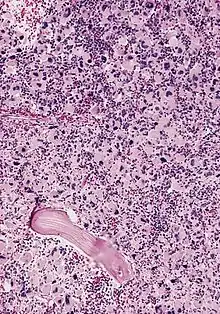

| AML-M7, bone marrow section | |